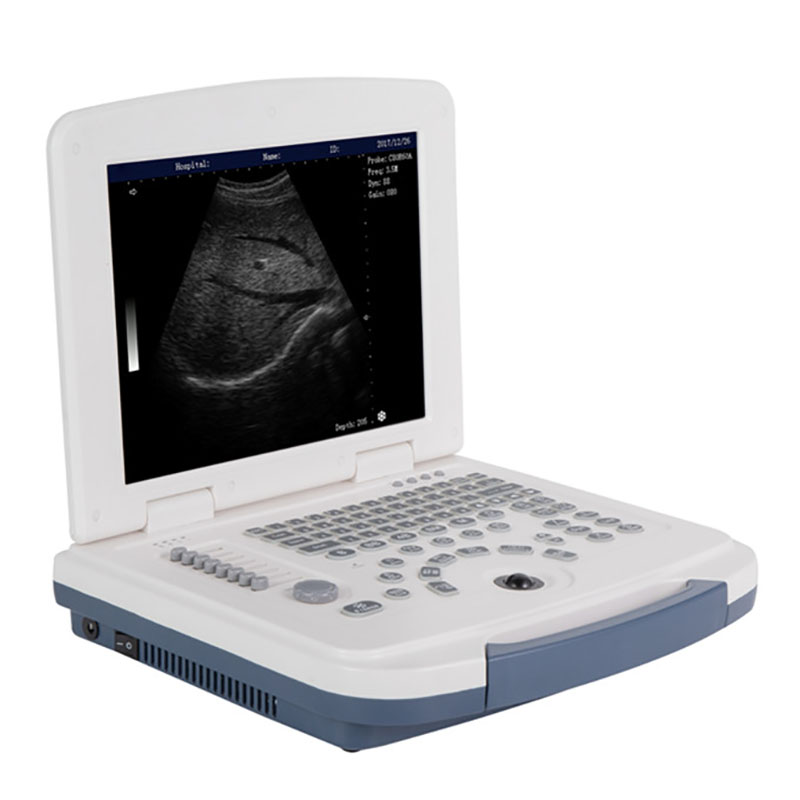

Máquina de ultrasonido portátil en blanco y negro RC-BW580

El ultrasonido portátil RC-BW580 es un equipo diagnóstico confiable diseñado para ofrecer imágenes precisas en una amplia variedad de entornos clínicos. Con una pantalla LED de 12 pulgadas y modos de imagen versátiles, como B, 2B, 4B, M y B&M, permite evaluar estructuras anatómicas con claridad y eficiencia. Su sonda multifrecuencia proporciona un rango de aplicaciones clínicas, desde abdomen y obstetricia hasta tejidos blandos y exploraciones musculoesqueléticas.

El RC-BW580 está equipado con reconocimiento de 65 marcas corporales, lo que facilita una mayor exactitud durante el examen y mejora el flujo de trabajo del profesional. Su batería de larga duración (3–5 horas) lo convierte en una solución ideal para clínicas móviles, consultorios, zonas rurales y atención domiciliaria.

La portabilidad del sistema, junto con sus puertos USB y entradas para sondas adicionales, garantiza flexibilidad y compatibilidad con diferentes configuraciones clínicas. Su diseño intuitivo y soporte multilingüe permiten un uso sencillo incluso en entornos de alta demanda. En conjunto, el RC-BW580 es una herramienta esencial para médicos y especialistas que requieren un ultrasonido práctico, eficiente y accesible.

El RC-BW580 es una máquina de ultrasonido portátil en blanco y negro diseñada para ofrecer diagnóstico eficiente en diversos entornos clínicos. Cuenta con una pantalla LED de 12 pulgadas, modos de imagen versátiles (B/2B/4B/M/B&M) y soporte multilingüe, lo que facilita su uso en distintos escenarios médicos. Su sonda multifrecuencia y capacidad para reconocer 65 marcas corporales permiten obtener imágenes precisas. Además, su batería de larga duración (3-5 horas) y puertos USB y de sonda hacen que sea una herramienta portátil y confiable para profesionales de la salud.